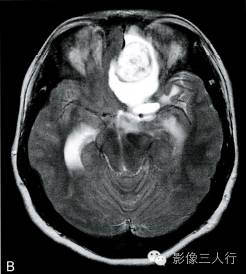

A.T1横断面;B.T2WI横断面;C、D、E~增强横断面、矢状面、冠状面;F.HE×100

图A、B:T1WI、T2WI横断面,图C~E为增强横断、矢状位及冠状位。左额底部见一囊性肿物,囊内见一直径约28mm类圆形肿块,边界清,T2WI呈不均匀高信号为主,内混杂条片状稍低信号,T1WI呈稍低信号,周边见环形稍高信号;增强后病灶大部呈明显强化,内可见不规则无强化区;灶周见液性信号影环绕,并可见大片状不规则水肿,累及左额颞叶、左基底节前部及左侧胼胝体膝部;邻近脑组织受压明显,左侧脑室、右侧脑室前角、3脑室及鞍上池受压变形,前部中线结构右移。